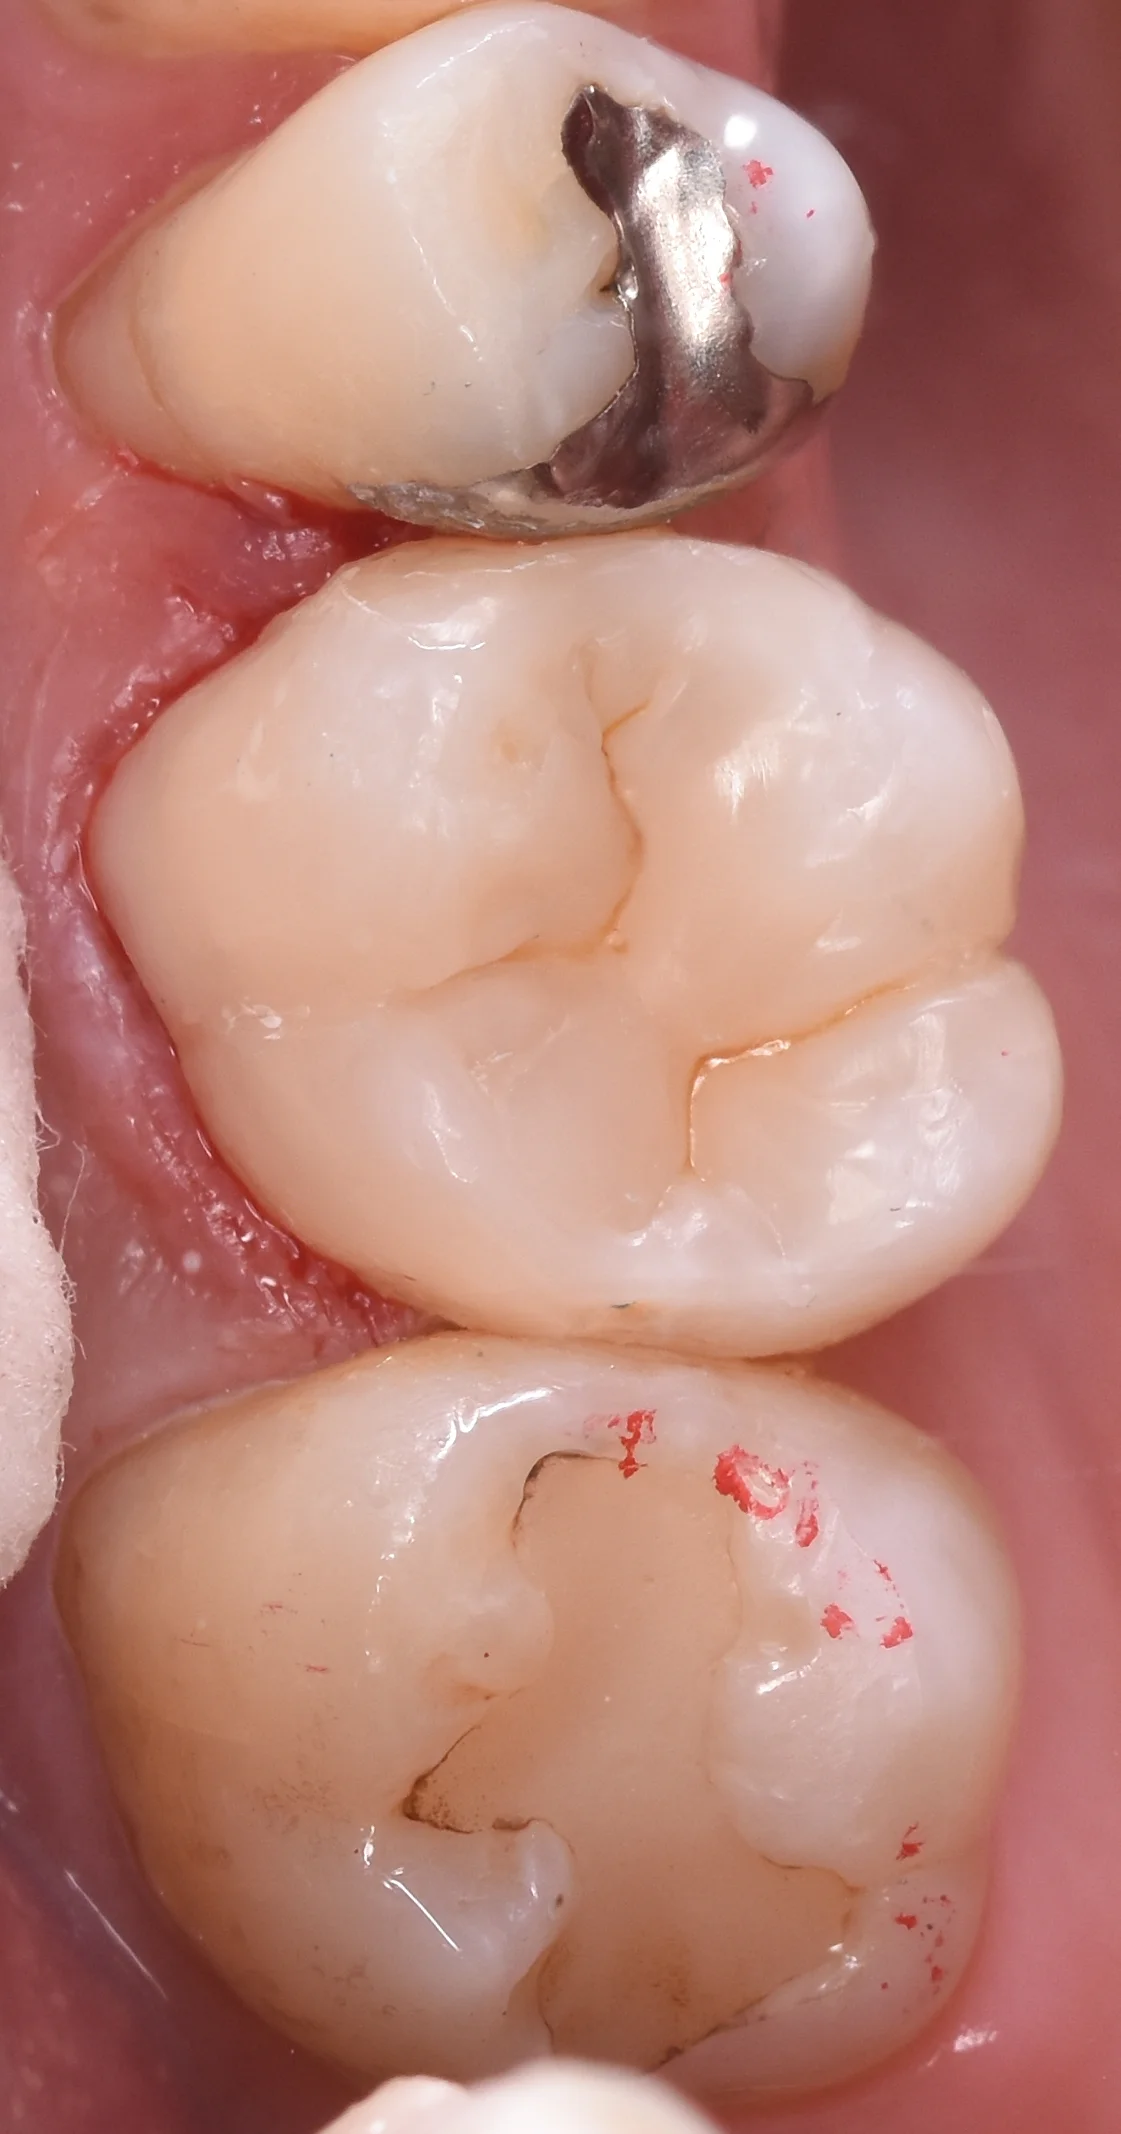

そして金属も除去し、白い詰め物も除去し切ったのがこちらになります。

金属を白い詰め物に。|坂寄歯科医院(取手市藤代) - 画像2

画像の上側の部分がほとんど歯がない状態になってしまっており、大体2/3の歯がなくなっている状態でした。

金属の詰め物が非常に綺麗に入っていたため、残存している歯に亀裂などは生じていなかったですね。